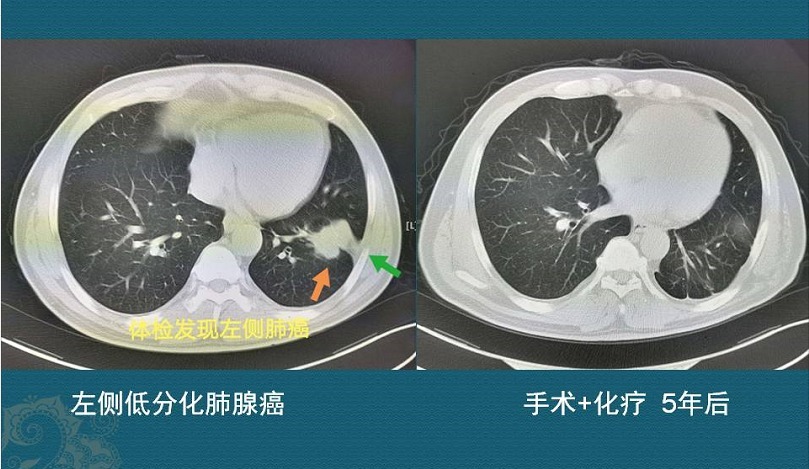

这是一位中年男子,从我们邻市慕名而来,左下肺腺癌接近5厘米,侵犯胸膜,肺门侧淋巴结转移,手术切除配合术后化疗,今年已经第6年了,没有复发!手术+化疗,治愈了!有手术机会的癌症,都有治愈的希望!